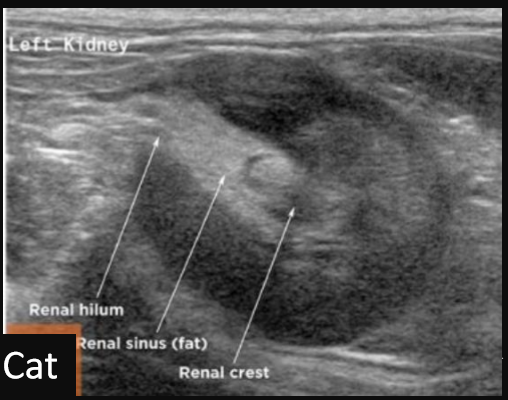

10

Q

Label this sagittal view kidney ultrasound

A